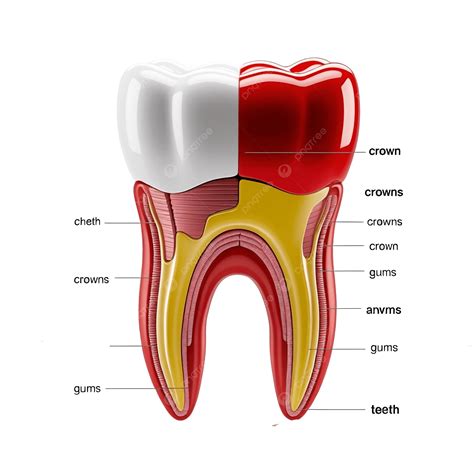

Componentes del Diente

- La Corona: La corona es la parte visible del diente, es muy dura y consistente, esta parte es la que determina la función de la pieza dental.

- La Raíz: Es la parte del diente no visible que se inserta en el hueso y está formado por dos terceras partes de la pieza dental. Cada pieza dental puede tener de una a tres raíces dependiendo el tipo de pieza.

- La Dentina: Es la parte del diente que se sitúa justo debajo del esmalte y su función principal es soportar el esmalte y transmitir impulsos nerviosos desde la raíz a la pulpa dental o al nervio del diente.

- La Pulpa: Tejido blando situado debajo de la dentina, en la pulpa se encuentra todo el sistema nervioso y vasos sanguíneos. proporciona vitalidad y protección al diente. Responde a estímulos como la presión o temperaturas.

- Las Encías: Son las encargadas de proteger las piezas dentales contra agentes patógenos alojados en la boca, por este motivo suelen acumular placa bacteriana y sarro. Es una zona extremadamente sensible debido a la exposición a las bacterias que pueden provocar gingivitis u otras enfermedades relacionadas.

- Esmalte: La capa más dura y externa del diente, diseñada para resistir el desgaste diario.

Anatomía de un diente.